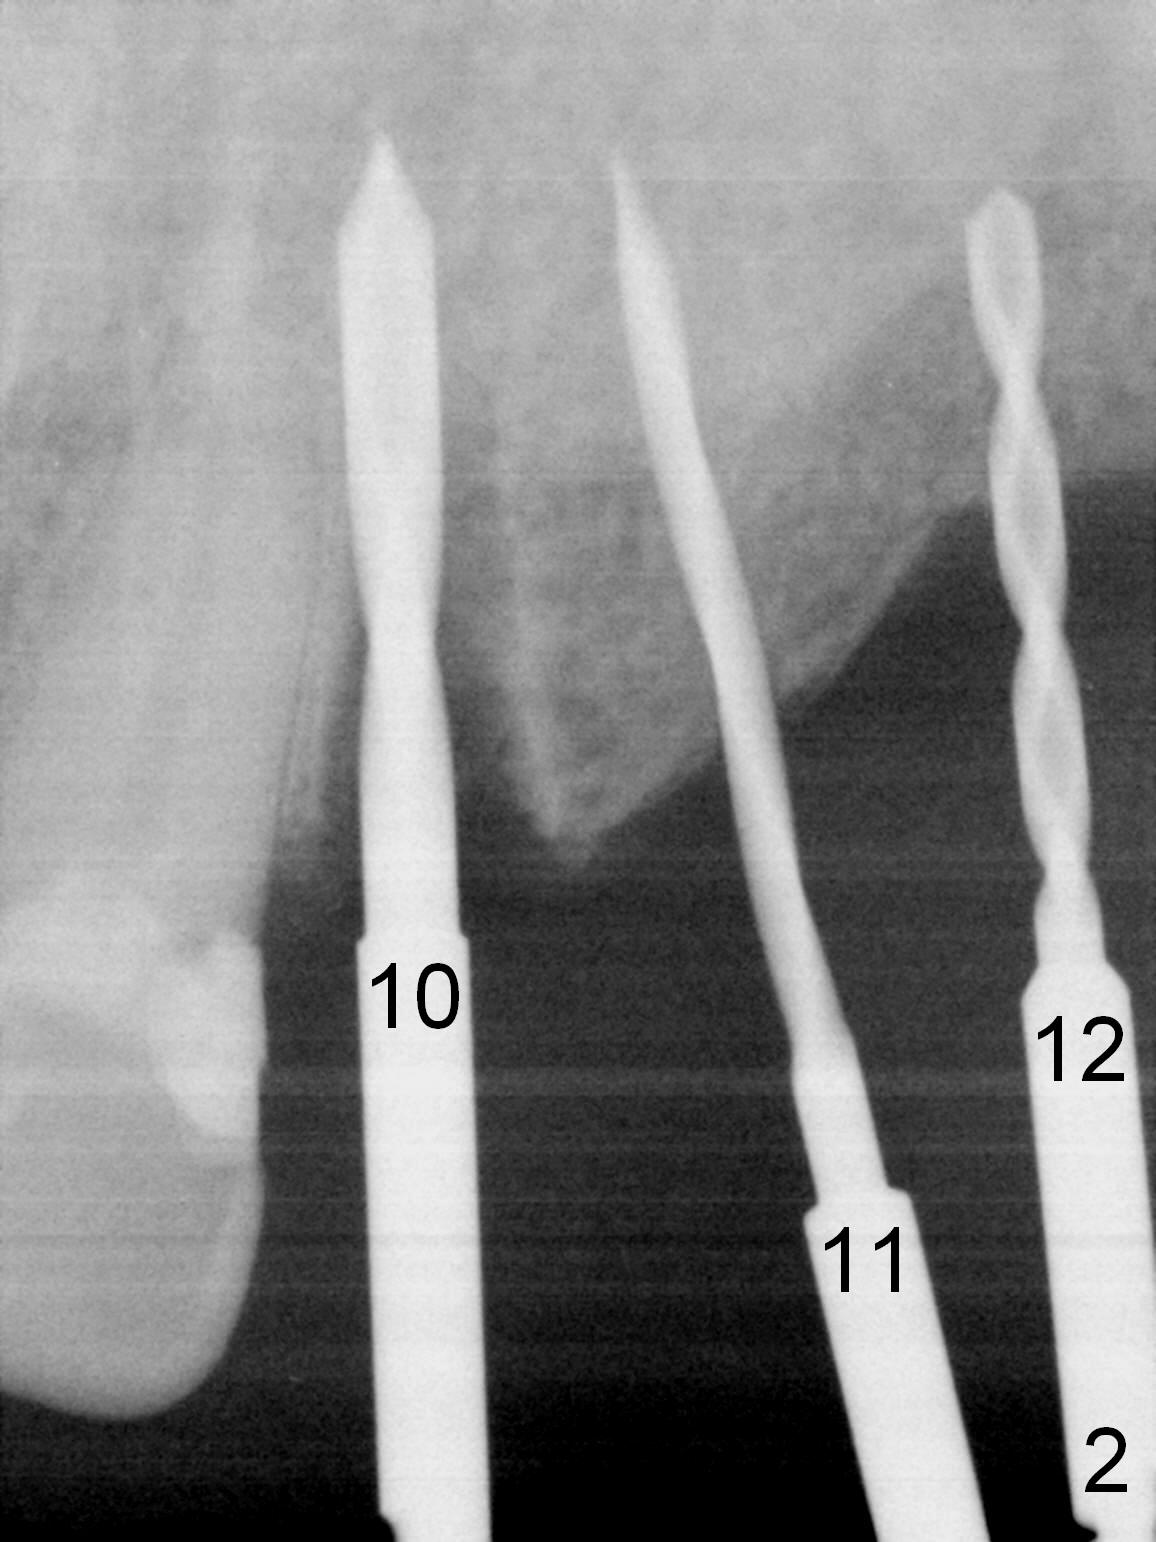

When the patient returns for implant placement (2nd visit after initial exam), he reveals that he is a dental phobic. He requests placement of 4 implants in the upper left quadrant, instead of 2. Narrow ridge is unexpected in the canine and premolar area (Fig.1). Limited bone height at #13 (Fig.3 arrowheads: sinus floor) is found when initial drills are in place (Fig.2,3). A 2-piece implant (4.5x17 mm tissue-level) is placed at #10 after extraction, while 1-piece implants are placed at 11 (3x17 mm (tissue-level, 15 °) and 12 and 13 (bone-level, 2.5x14, 12 mm, respectively; Fig.4,5). In fact the 1 piece implant at #13 is not completely placed (Fig.5). It is removed, the apical 3 threads are cut off (Fig.6 <, since a shorter implant was unavailable in the office) and the remaining implant is re-inserted. The insertion torques of the 4 implants are ~ 60, ~ 35, < 35 and 15 Ncm, respectively. After adjustment (Fig.7), immediate provisionals are fabricated at #10 and 11 (Fig.8, later splinted with composite), while perio dressing is applied around the implants at #12 and 13 and the provisionals at #10 and 11. There is no nasal hemorrhage postop. Although the perio dressing is loose 1 week postop (Fig.9), it is not removed. When the upper lip fissure (Fig.9 <) heals, provisionals at #12 and 13 are planned to be splinted to the other two ones. Two weeks postop, the upper lip fissure heals, the perio dressing dislodges and the implants at #12 and 13 are stable (Fig.10). After abutment height adjustment, a splinted provisional is fabricated over these 2.5 mm 1-piece implants (Fig.11).